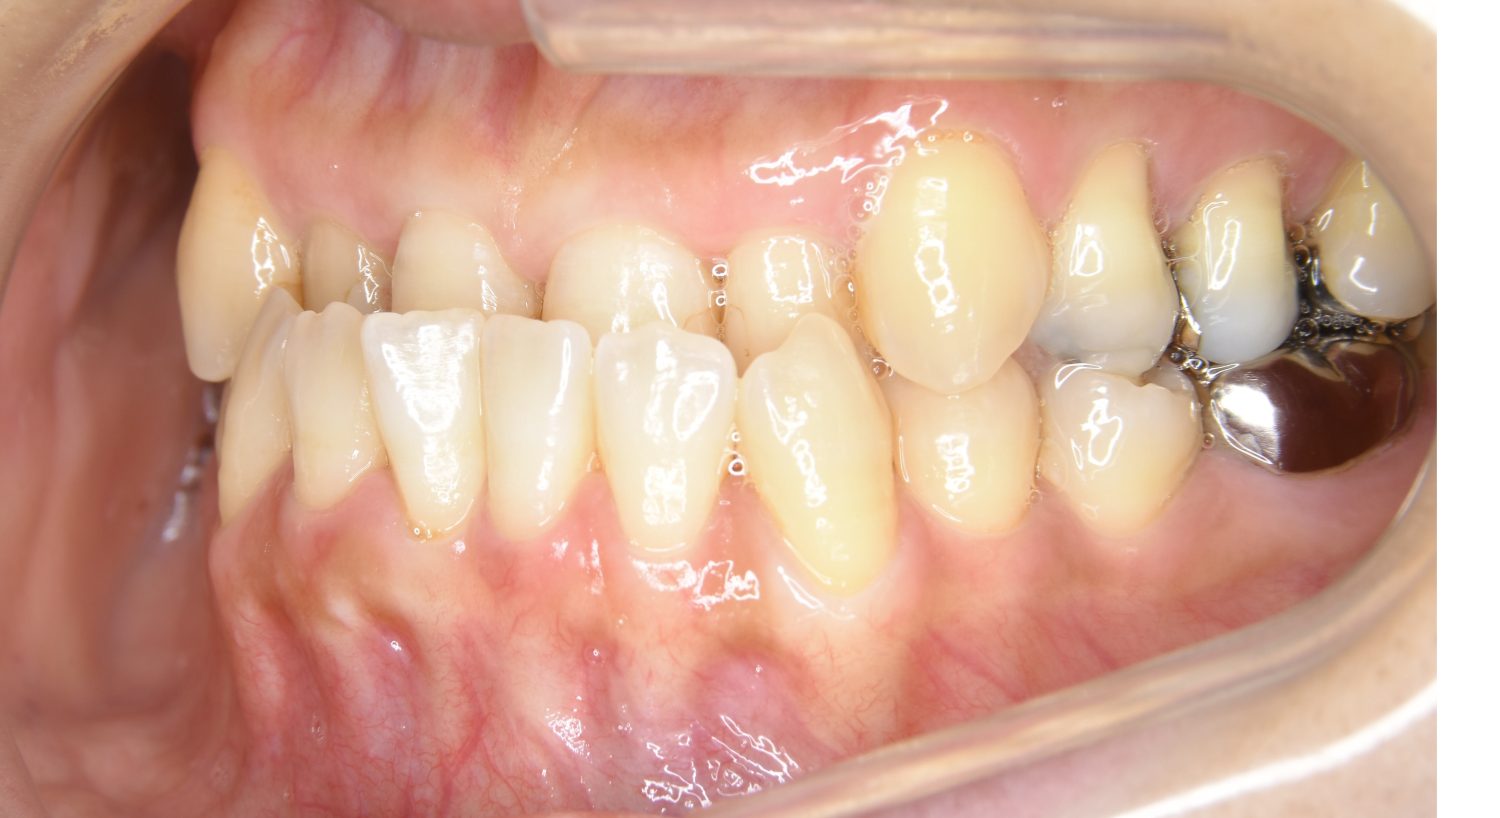

Before

主訴

前歯が開いているのが気になる。

治療内容

上リンガルブラケット(舌側装置)、下ラビアルブラケット(唇側装置)に矯正用アンカースクリューを併用し非抜歯で治療を行いました。

上下の前歯が開いており前歯では全く噛めていない状態でした。臼歯の圧下を行うことで前歯でも咬合できるようになり機能面のみでなく審美面も著しく改善しました。